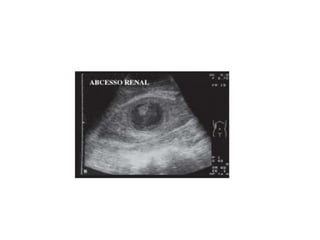

Complicações

• Agudas: Abscesso perirrenal, pionefrose,

orquiepididimite, necrose de papila renal e

sepse.

Complicações • Agudas: Abscessoperirrenal, pionefrose, orquiepididimite, necrose de papila renal e sepse. • Tardias: Insuficiência Renal crônica e Litíase urinária.